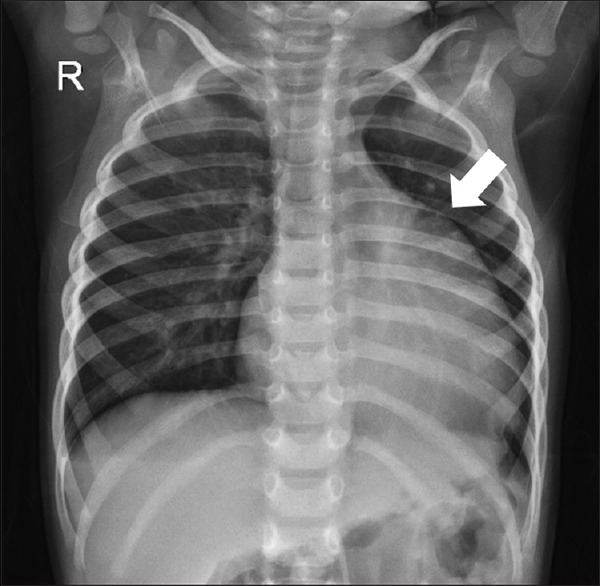

Absent pulmonary valve syndrome, commonly linked with tetralogy of Fallot and ventricular septal defect, is a rare congenital condition. It is exceedingly rare to have an isolated absent pulmonary valve with an intact ventricular septum without cardiovascular shunt lesions, such as an atrial/ventricular septal defect or patent ductus arteriosus. This report presents a case of such rarity involving a young child with recurrent lower respiratory tract infections.